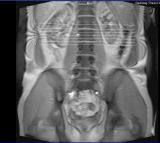

ich habe seit über 7 Jahren schmerzen in der LWS mit Ausstrahlung in den linken Hoden. Vor ca. 7 Jahren wurde auch ein MRT gemacht und da hieß es ich habe ein LWS Syndrom.

Nun sind die schmerzen heftiger geworden das ich manchmal nicht wirklich sitzen kann, weil es so doll im Hoden weh tut, auch ein komisches Gefühl in den Beinen ist dazu gekommen.

Nun war ich wieder beim Arzt und gestern erneut im MRT. Leider ist mein Arzt erstmal im Urlaub und ich muss 2 Wochen auf das Ergebnis warten, aber vielleicht könnt Ihr mir hier schon eine kleine Aussage machen wenn ich mal ein paar Bilder hier poste. Das wäre super von Euch.